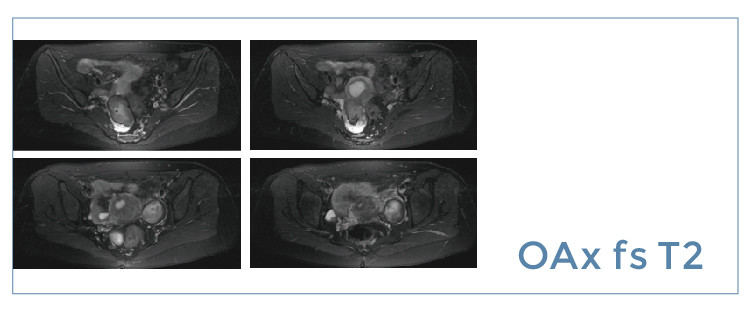

【朗润影像档案】20190705磁共振影像病例结果讨论